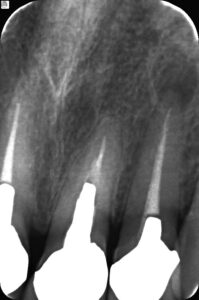

【右上2番】【左上2番】

【右上2番根尖病巣】【左上2番根尖病巣】

診断 フィステルは右上2番由来 根充剤が根尖まで充填されていない 主訴ではないが左上2番にも根尖病巣が認められる。通法どうり保存治療を行う。